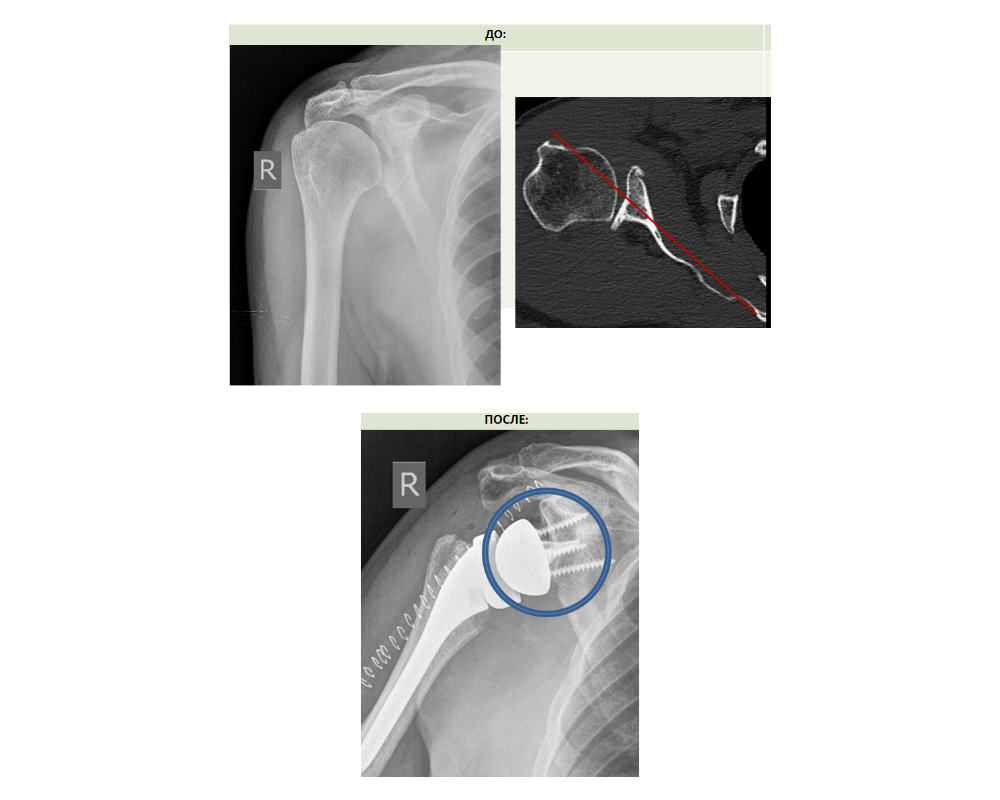

Возрастной пациент из Пермского края 8 лет назад при падении получил травму плеча. Лечился по месту жительства консервативно, и затем также без эффекта оперативно. Болевой синдром нарастал, а движения в суставе стали ограниченными.

Мужчине был поставлен диагноз - посттравматический артроз правого плечевого сустава III стадии с костным дефектом гленоида.

За особо сложный случай в хирургии крупных суставов взялись врачи отделения №8 Центра Илизарова. Они выполнили реверсивное эндопротезирование правого плечевого сустава с костной аутопластикой суставного отростка лопатки.

- Наиболее сложные случаи для имплантации эндопротеза, когда сформировался дефект кости суставного отростка лопатки. Если его не возместить, то фиксация лопаточного компонента эндопротеза либо не возможна, либо будет выполнена с нарушением биомеханики, что приведет в дальнейшем к вывихам в эндопротезе и его раннему износу, - пояснил руководитель Клиники реконструктивно-восстановительной хирургии крупных суставов, д.м.н. Николай Чирков.

У данного пациента для замещения дефекта и правильного размещения компонентов эндопротеза требовался костный блок, его взяли из головки плеча, сформировав аутотрансплантат. По сути это прокладка из собственной кости между лопаточным компонентом эндопротеза и дефектным суставным отростком лопатки.